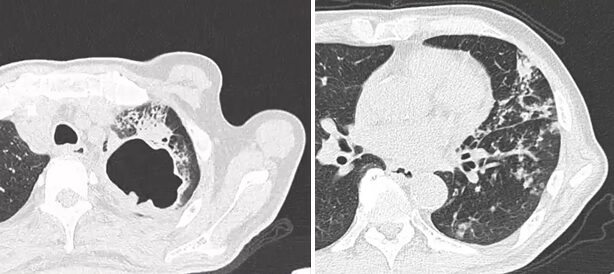

34歳男性。4~5前から続く右胸痛・咳嗽。2日前より呼吸困難感が出現。 SpO2 93(r.a) 呼吸音:右で減弱。 X-p: 右肺は高度虚脱。 縦隔の左方変位…